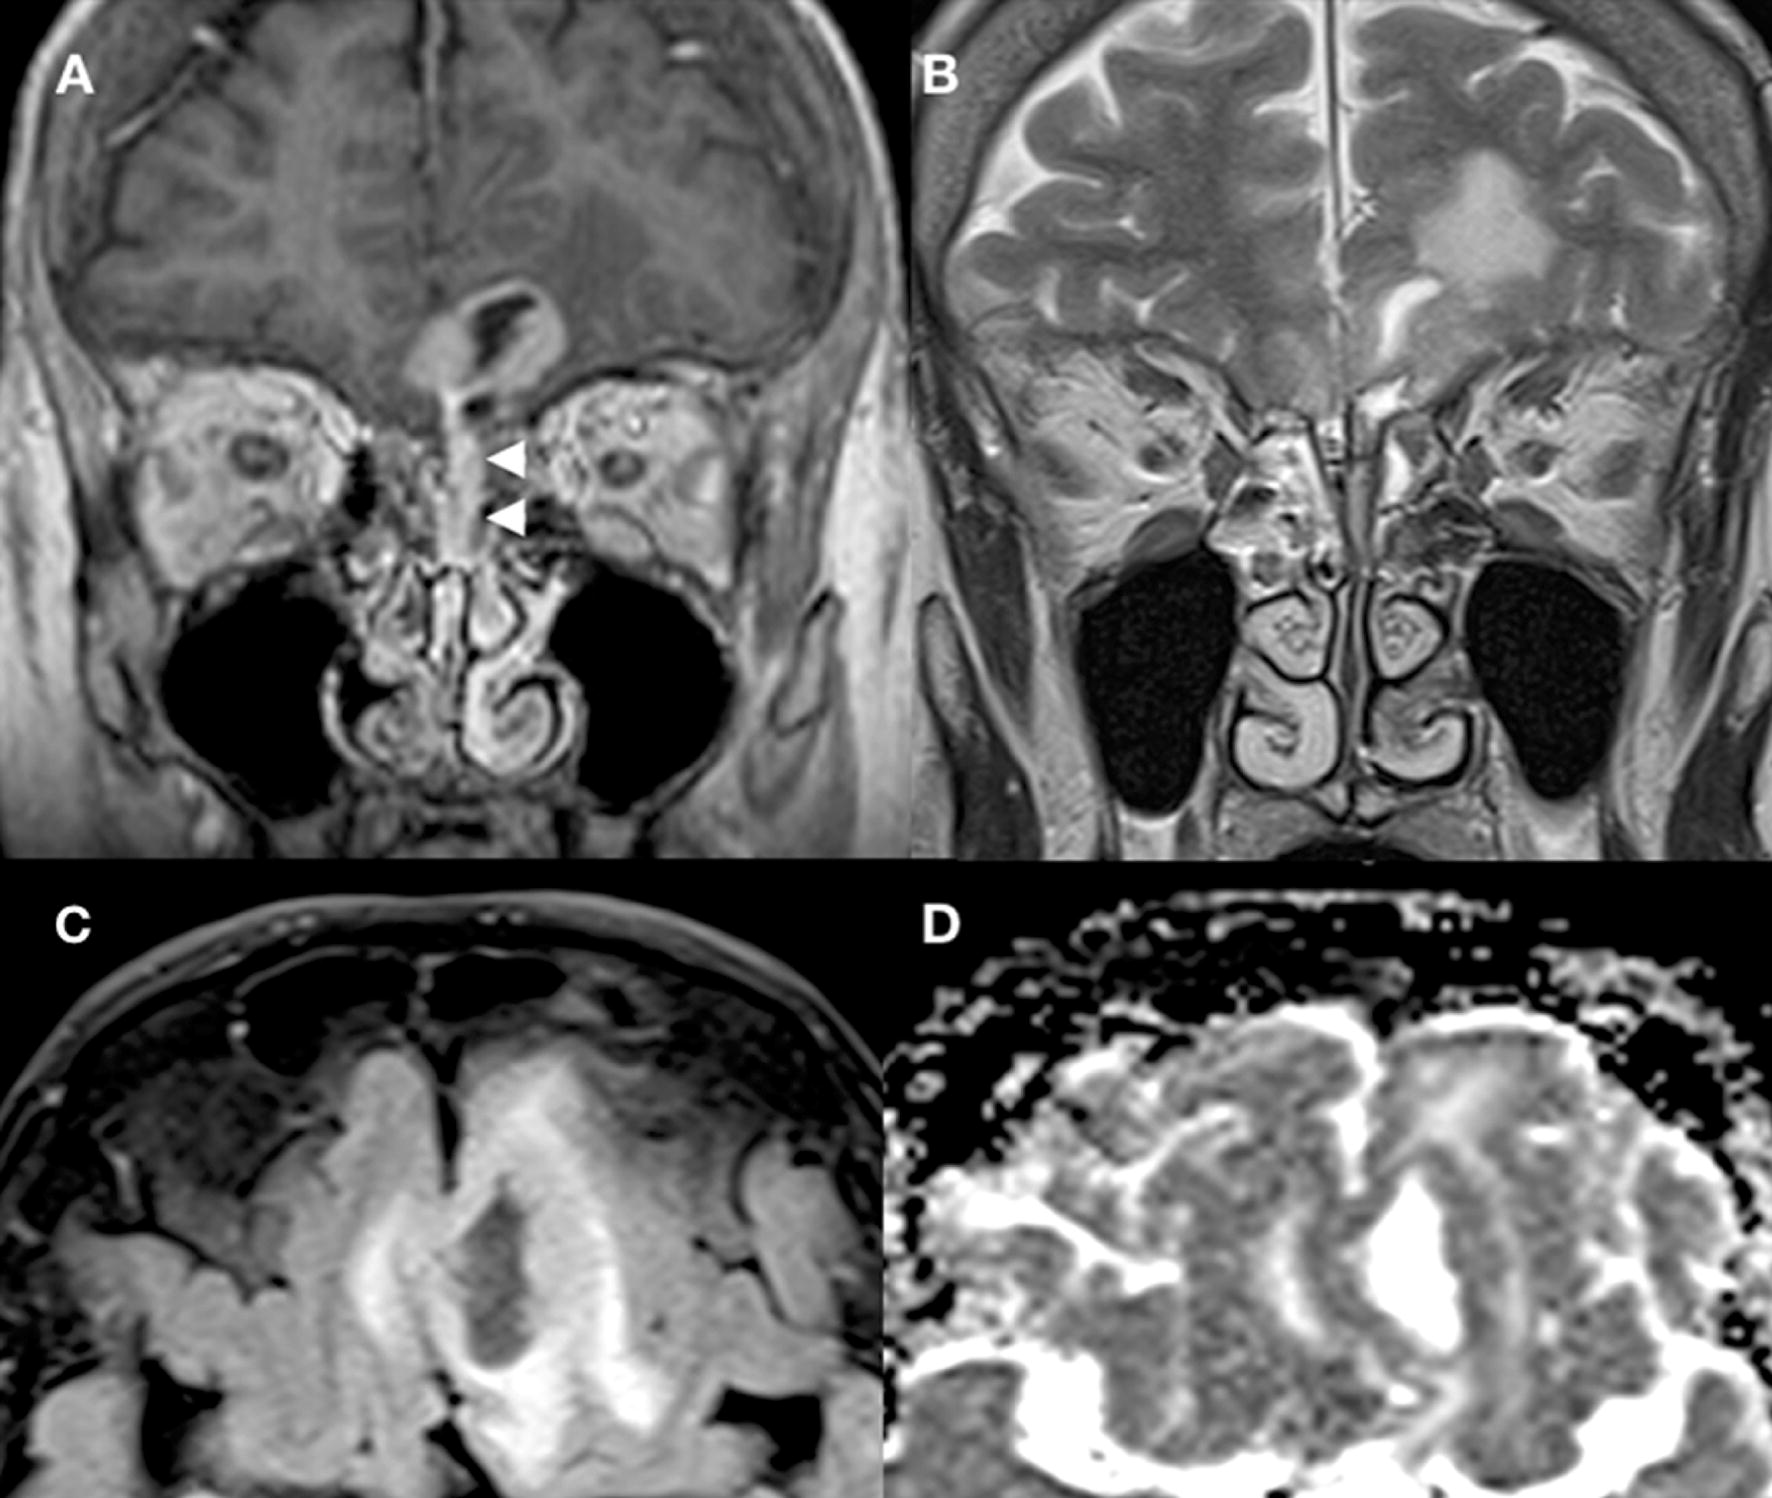

MRI scan of the head revealed a cystic mass extending from the left nasal cavity into the anterior cranial fossa, associated with vasogenic oedema at the base of both frontal lobes (Fig. 1). There was minor midline shift to the right and minimal effacement of the anterior horn of the left lateral ventricle, but no evidence of hydrocephalus or haemorrhage. The patient was given dexamethasone for reversal of cerebral oedema and levetiracetam for seizure prophylaxis. Computed tomography (CT) scan of the thorax, abdomen and pelvis showed no evidence of disseminated malignancy (modified Kadish stage C, Dulguerov stage T4N0M0, Biller stage T3N0M0). The case was discussed in the neuro-oncology multi-disciplinary team meeting, and the decision was taken to offer an endoscopic-guided anterior skull base biopsy.

Fig. 1

MRI of the anterior skull base. Coronal T1 post-contrast (a) and coronal T2 (b) demonstrate a mixed solid cystic mass extending from the olfactory recess of the left nasal cavity (white arrowheads) through the left cribriform plate and into the anterior cranial fossa. The mass is adhered to the pial surface of the frontal lobes of the brain bilaterally. There is adjacent vasogenic oedema within the brain parenchyma on the coronal T2 (b) and axial FLAIR (c) sequences. The solid portions demonstrate avid enhancement (a) and intermediate to restricted apparent diffusion (d) consistent with a cellular neoplasm